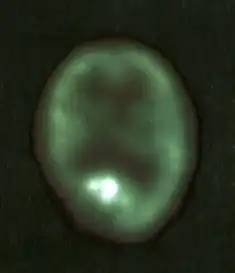

Positronen-Emissions-Tomographie

Die Positronen-Emissions-Tomographie (PET) als funktionelles bildgebendes Verfahren (sie gibt, vereinfacht gesprochen, die Stoffwechselaktivität bildlich wieder) erlaubt die Beantwortung spezieller Fragen. Eine solche wäre zum Beispiel die Unterscheidung eines lokalen Rezidivs von einer Strahlennekrose unter der Behandlung, wenn diese Differenzierung nicht aus der Kernspintomographie allein abgeleitet werden kann.[10]